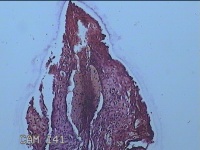

宫颈管组织

性别

女

年龄

33岁

临床诊断

异位妊娠

一般病史

停经52天,阴道流血12天。

标本名称

大体所见

灰白暗红色不规则碎组织4.3x3.3x1.2cm一堆。